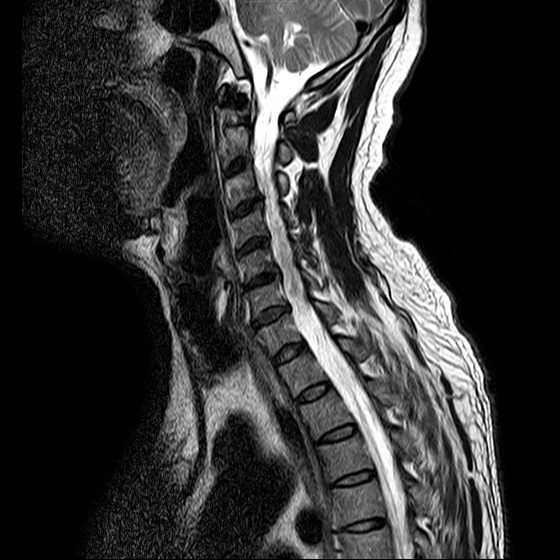

ũ Ͻ е鲲 ǰ ϴ. ڸ 4°Դϴ. ũ ϴ. (ڸǥغ ǥغ ) @ : 2014. 2.15 ĺ Ȳġ Ͽ. -> κ ǿ ġϿ պ ϱ. @ 2014. 3. 27 к mri, ct ũ ϰ ؾ Ѵٰ. @ ũ ġ ͳ Ͽ ڸǥغ Ͽ. ϱ : .(ó ) 2014. 4. 12() --- <1°> : Ͽ ȸ . 㳻 : (ڱ , Ӹ е ħ ˷. ¿ . ų ɰų Ҷ ̰ų ڼ . 201.4. 4. 13() ---<2°> 1. ħ Ͼ ¿ ȭ . 2. ħ е ħ . 3. ü ƮĪ ˷. ڼ ˷ֽŴ ϸ ڼ ùٸ ϸ Ÿ ˷ֽ Ư ƮĪ ϸ Ѱ پ 2014. 4. 14() ---<3°> : : پ(ó ߴ.) 㳻 : 1. ħ Ͼ ¿ ȭ . 2. ũ ˷ . 2014. 4. 14() ---<4°> : پ(ó .) 㳻 : 1. 繫ǿ ũ ٽ 2. ũ ˷ ϸ ڼ ϸ ȸ ̷ ɴ 2~3 ϸ ȸȴٰ Ͻô ū 븦 Ͽ ȸϵ ϰڽϴ. ȸ Ź帳ϴ. ũ mri Ȳ Դϴ. Ű 179 86 51 ()ijħ ڸǥغ ǥغ ˰Ե ͳ ˻ڷ õ ()ijħ ڸǥغ ǥغ ϱ ȣϽ 6C.ڸ 6C.ھ Ḳ 7C.Ȳġ 1T.Ȳġ 1T. κ ()ũ( ߰Ż) ڸ(߹) ũ(߰) Ը ũ(߰Ż)ġ, ()ijħ ڸǥغ ǥغ ϰ ߴ ġ 1. : 2014. 2.15 2. ġ : Ʒ(ô߿ ) , ȱ 3. **뺴 : ˾. Ƽ (ũ ) 4. ó : ڰ, 3 Ⱓ mypol()ó. ȭ. 3 5. ü ġ . |